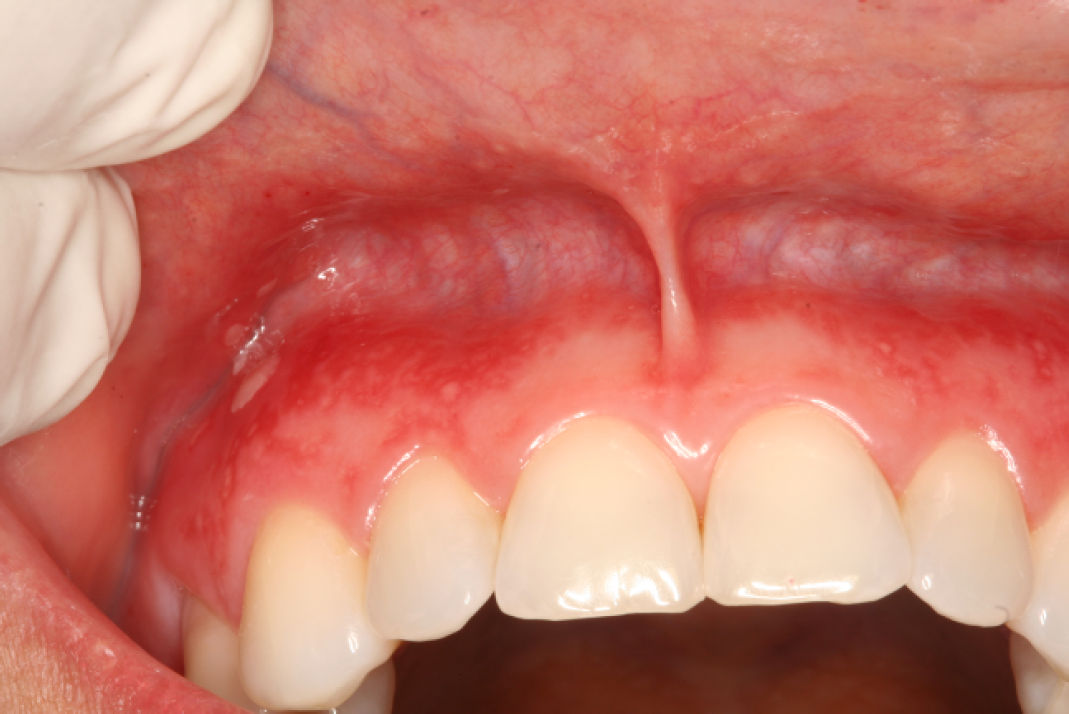

При клиническом осмотре были выявлены множественные болезненные мелкие округлые язвы на прикреплённой десне переднего отдела верхней челюсти и на прилежащей альвеолярной слизистой. Пациентка сообщила, что поражения появились около месяца назад, ранее подобные эпизоды отсутствовали. Кожные поражения не обнаружены.

Фото 1. Множественные мелкие округлые язвы на прикреплённой вестибулярной десне верхней челюсти и прилежащей слизистой оболочке губы